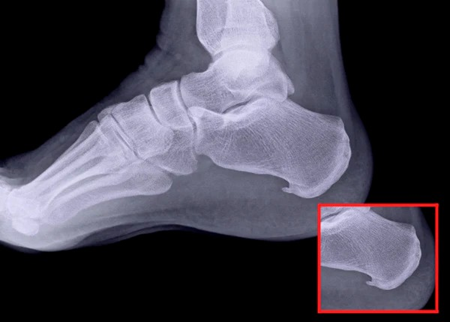

A heel spur is a calcium deposit causing a bony protrusion on the underside of the heel bone. On an X-ray, a heel spur can extend forward like a hook. Many calcaneal spurs are asymptomatic and pain usually comes with associated soft tissue inflammation.

Heel spurs are your body’s response to stress and strain placed on your foot ligaments and tendons. You can also develop heel spurs by repeatedly tearing the covering that lines your heel bone. Repeated Stress on your heel from walking, running or jumping causes Calcaneal spurs. Obesity also puts excess pressure on your feet. Aging leads to reduced flexibility in the plantar fascia. Altering pressure distribution on the heel due to flat feet or high Arch also causes Calcaneal Spur.